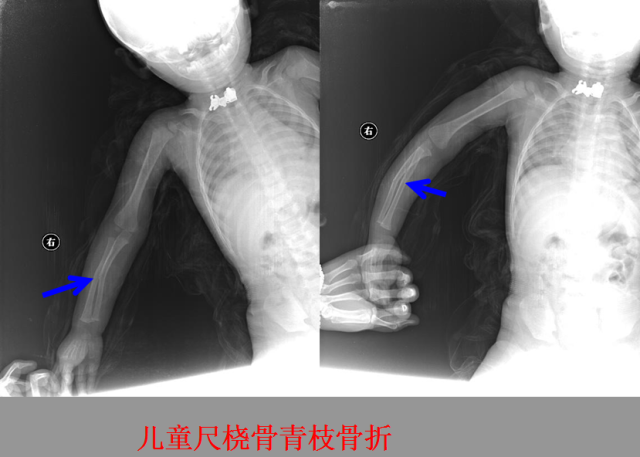

骨折篇

01

定义:骨折{Fracture}是指骨的完整性和连续性的折裂或粉碎。包括创伤性骨折、疲劳性骨折和病例理性骨折。 临床上以创伤性骨折*常见。